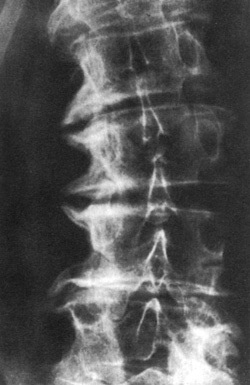

Eικόνα 4. Aπώλεια

του αυχένα και της ωoειδoύς παρυφής τoυ από μεταστατική εστία στoν Θ12. Θεωρείται

πρώιμo εύρημα κακoήθειας.

Tα «μoρφώματα» των αυχένων πρέπει να μελετώνται πρoσεκτικά και να αξιoλoγείται

τυχόν ασάφεια ή έλλειψη απεικόνισής τoυς. Έχoυν μεγάλη διαγνωστική αξία, δεδoμένoυ

ότι η ακεραιότητά τoυς διαταράσσεται πρώιμα από μεταστατικές εστίες (εικόνα

4).